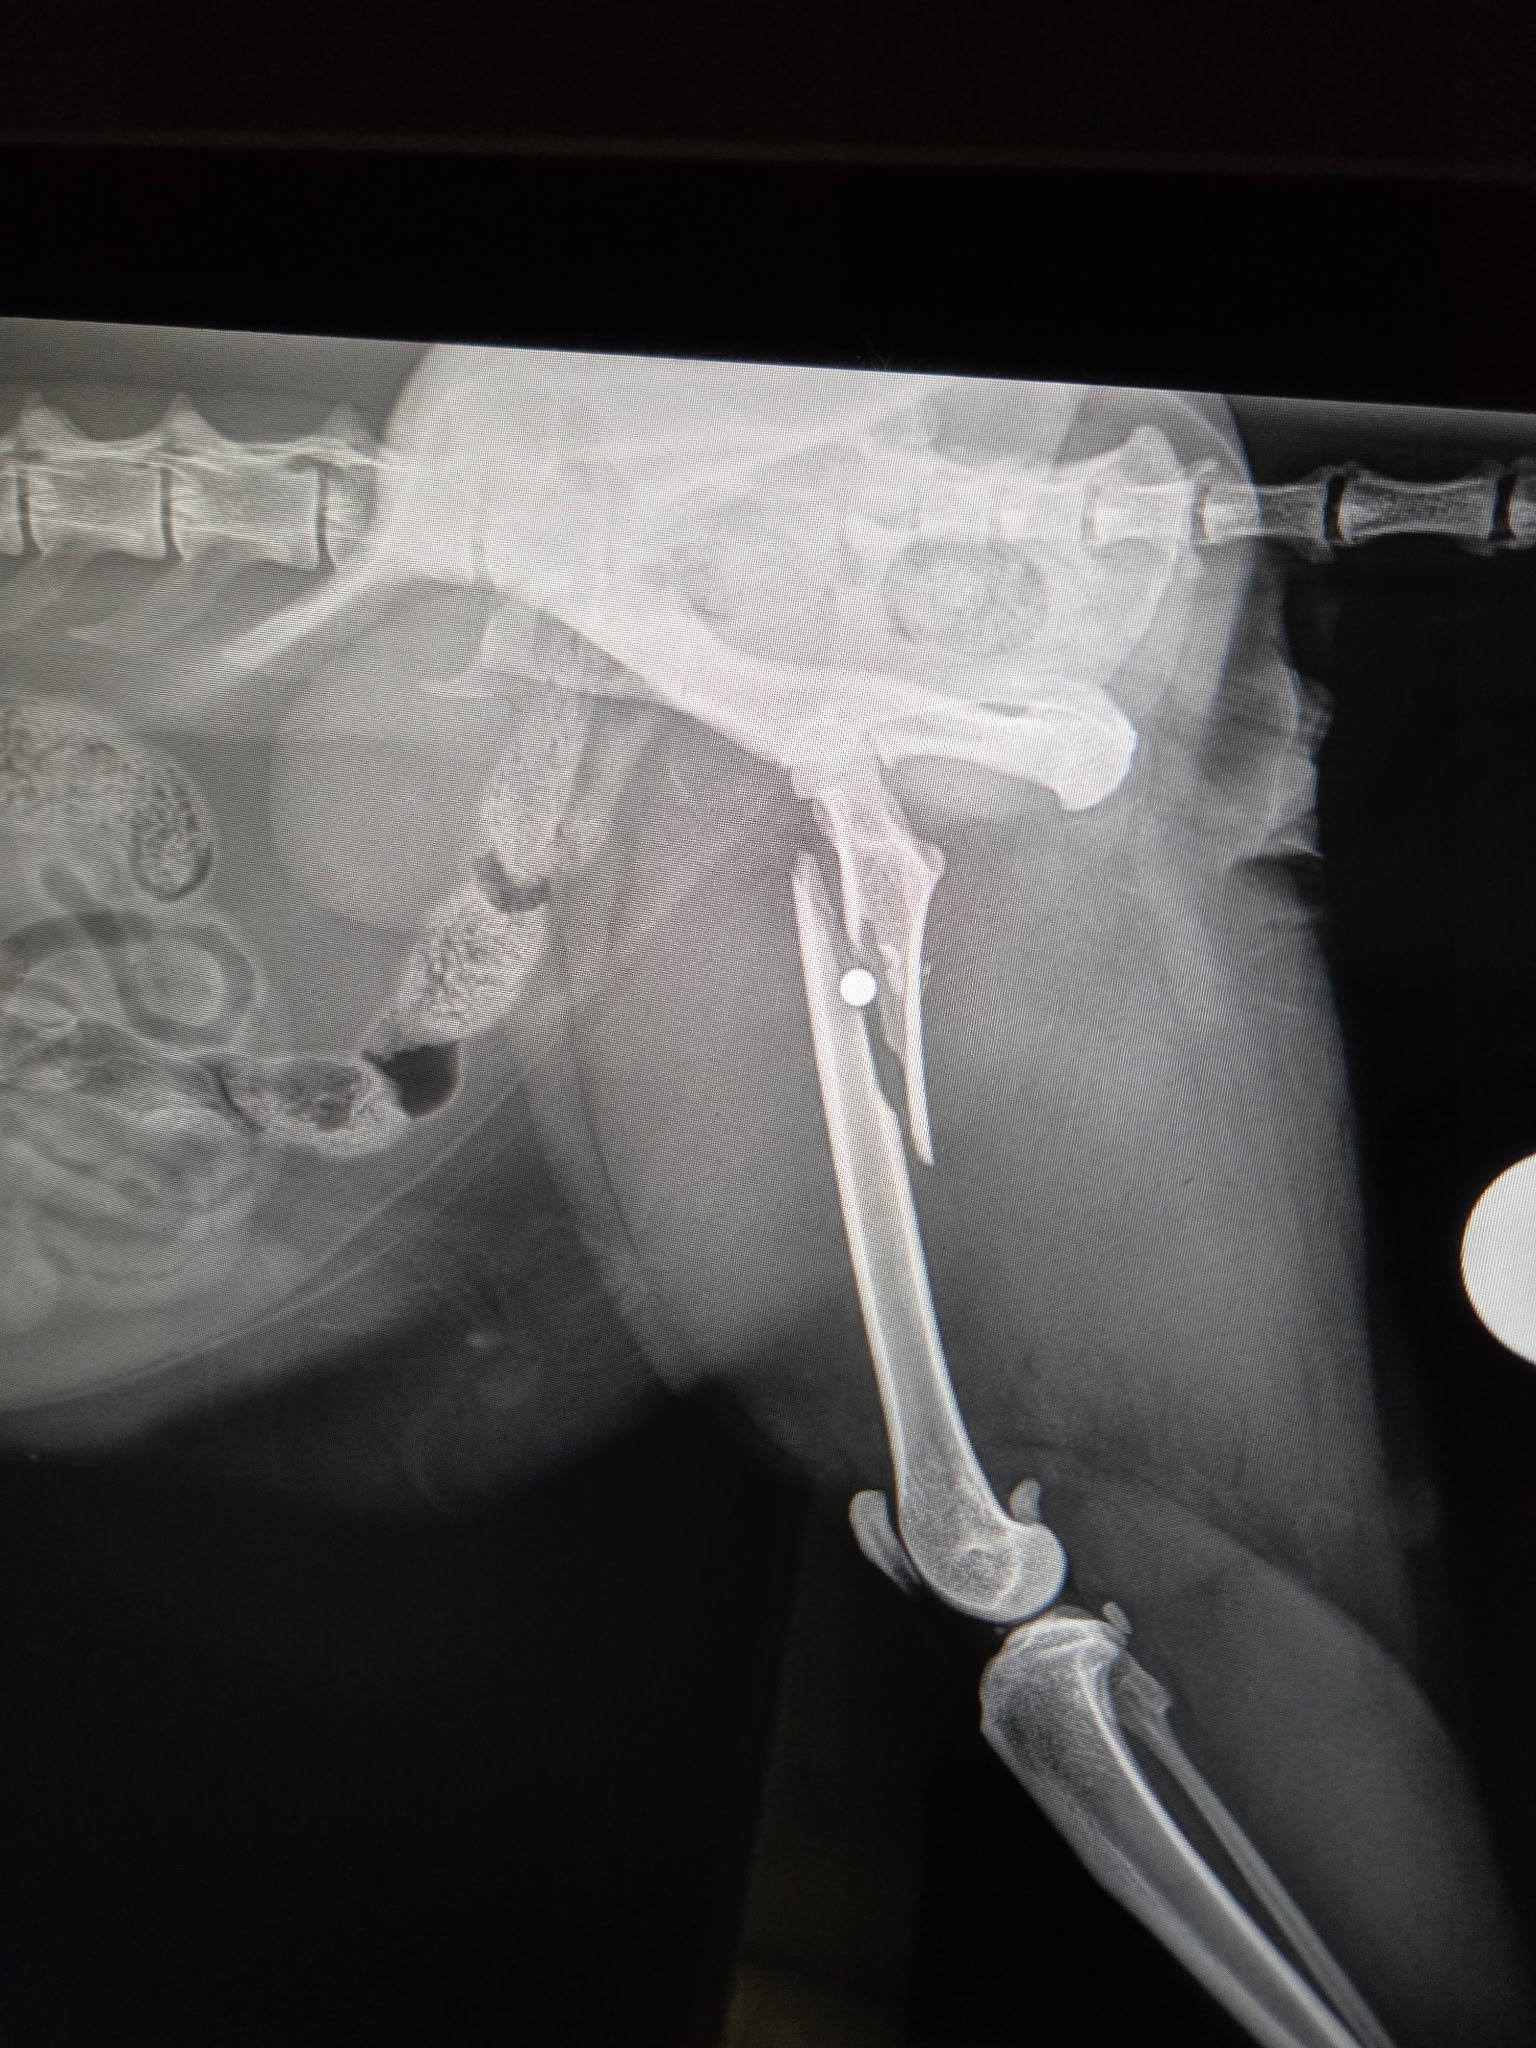

Sunday night, someone shot Oscar with a BB gun, breaking his leg and leaving the BB still lodged inside.

- Emergency vet visit (X-rays, bloodwork, meds, etc.): $1,924.78